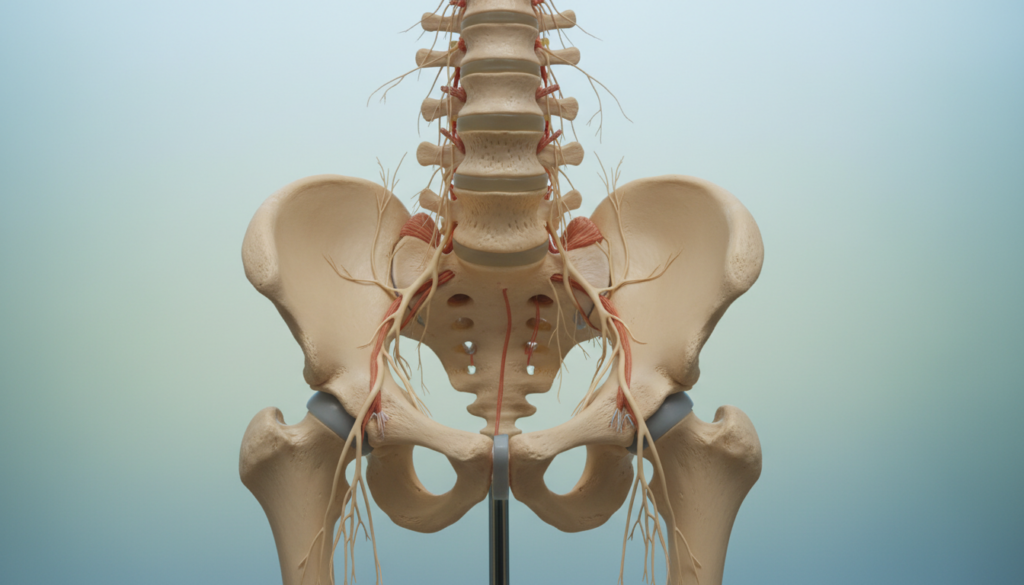

Anatomie und Ursachen: Verbindung von unterem Rücken, Becken und Nerven

Die Verbindung zwischen Becken und Wirbelsäule ist entscheidend für schmerzfreie Bewegung. Hier treffen verschiedene Strukturen zusammen.

Das Iliosakralgelenk bildet das Zentrum dieser Verbindung. Es überträgt Kräfte zwischen Oberkörper und Beinen.

Funktion des Iliosakralgelenks

Dein Kreuzbein verbindet die Lendenwirbelsäule mit dem Becken. Diese Stelle heißt Iliosakralgelenk.

Das Gelenk ist straff und beweglich. Es ermöglicht kleine Anpassungen bei jeder Bewegung. Langes Sitzen macht es steif.

Beteiligte Muskeln und typische Verspannungen

Die Muskulatur um das Becken arbeitet als Einheit. Verspannungen haben direkte Auswirkungen.

Der Piriformis-Muskel im Gesäß liegt über dem Nerv. Seine Verspannung kann Druck verursachen.

Verkürzte Hüftbeuger ziehen am Becken. Das belastet die gesamte Rückenmuskulatur.

Eine stabile Becken-Wirbelsäulen-Verbindung ist die Basis für schmerzfreie Bewegung.

Die Ursachen sind meist muskulär. Verspannte Muskeln, blockiertes Gelenk, Druck auf Nerven. Die Lösung heißt: Mobilisation und Dehnung.